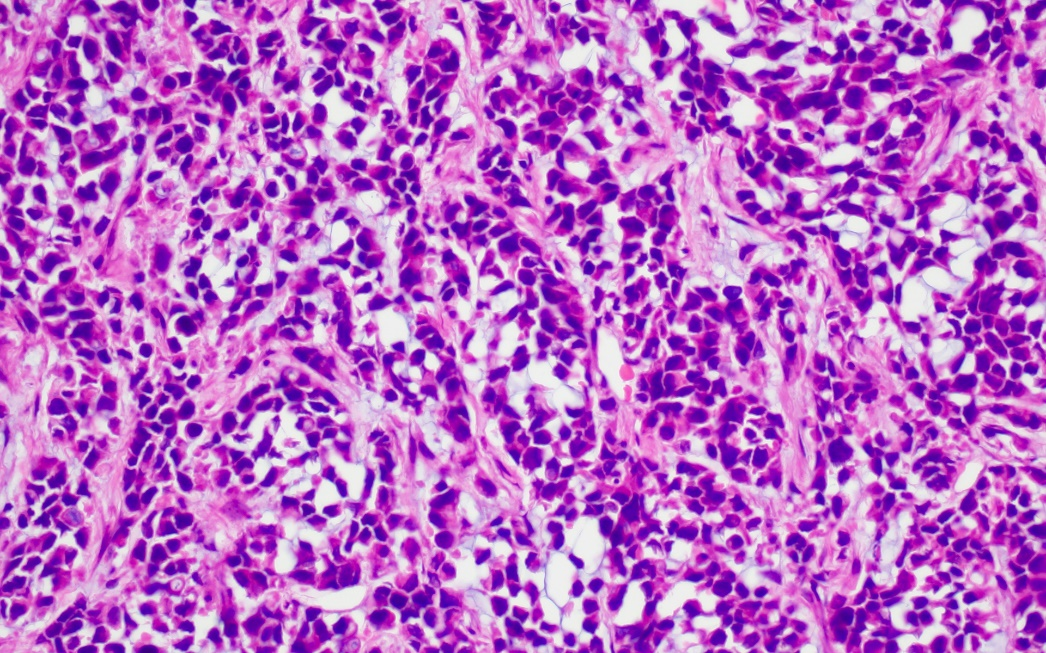

病理:符合胃癌病理特征

圖片5.png

圖片6.png